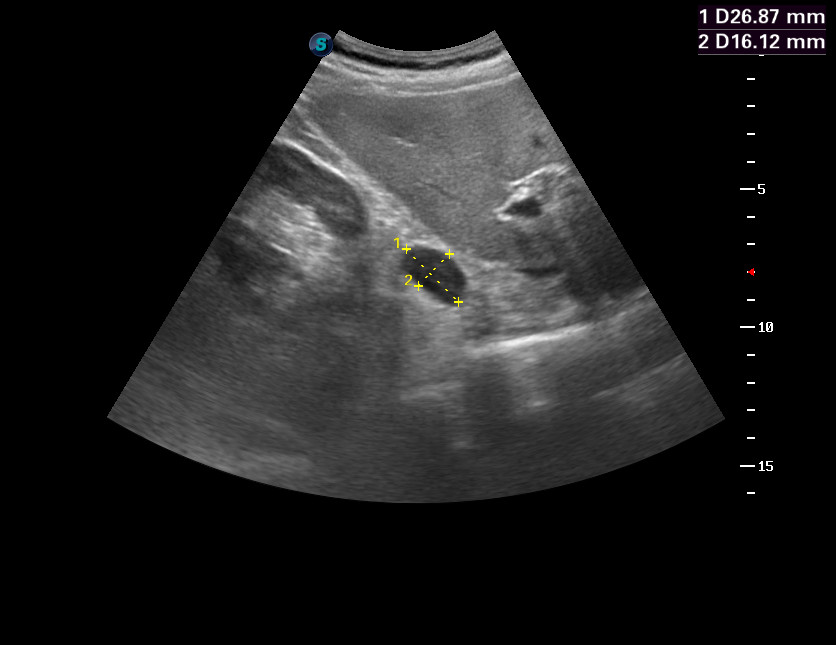

Последняя сонограмма - подсказка.servik писал(а):что то забрюшинное? типа лимфо липо саркомы?

надпочечник?

Если анемия, то мтс

Логично.Брехт писал(а):Если анемия, то мтс

Повторное исследование через 6 мес. Уже есть данные о карциноме простаты.